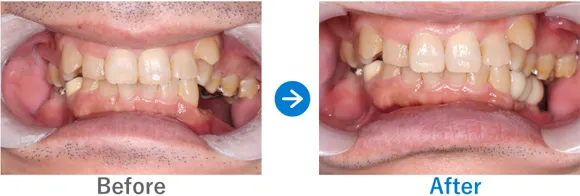

上下義歯(入れ歯)ほとんど歯が残っていない、残存歯は上顎1本下顎5本のみ。

上顎骨がやせていて普通にはインプラントが出来ない状態。

上顎ザイゴマインプラントでALLON4、下顎ALLON4

治療結果

上顎ザイゴマインプラント4本。下顎ALLON4で行った。治療完了後、現在もメンテナンスで来院中で経過良好。口元が綺麗になり、お化粧をするなど美意識が高まり、おしゃれに気をつかうようになったとのこと。「笑顔が増えて、よく外出するようになりました。自信がつきました。」